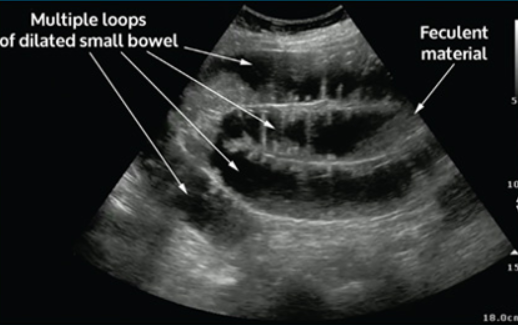

Bowel obstruction